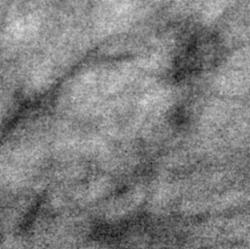

После цифровой обработки изображения (1, 2) и выделения «навигатором» участка с патологическим образованием (4, 5) определяется локально участок перестройки структуры, на фоне которого определяется несколько макрокальцинатов. Аналогичный макрокальцинат располагается несколько ниже.